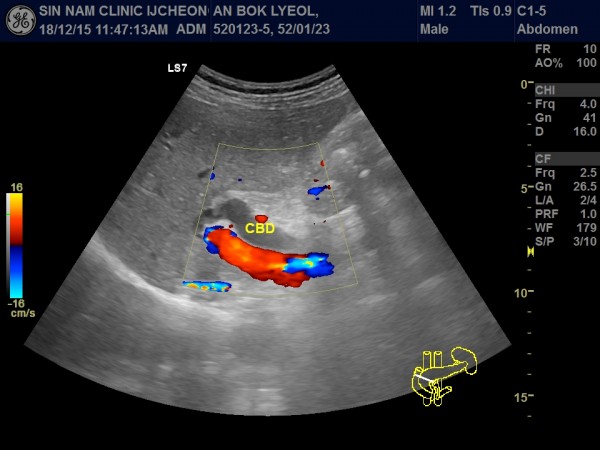

담관암, 담도암, 상복부 초음파